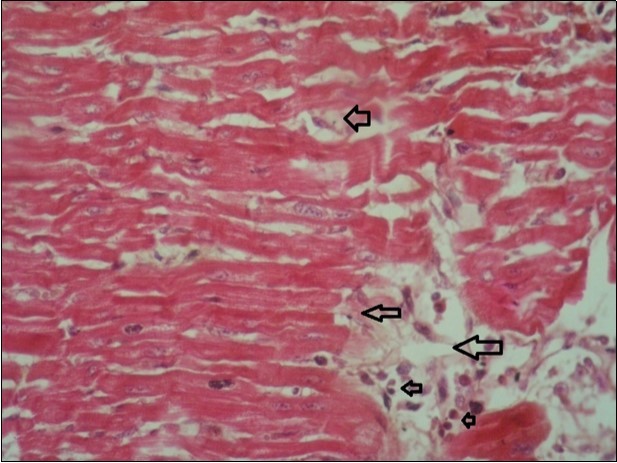

Figure 10.Heart (dead cattle less than 1 year old) showed area of extravasated blood with few inflammatory WBCs (arrows). (Hematoxylin and fuchsin X 40)

Figure 11.heart (dead cattle less than 1 year old) showed vesicular nuclei of myocytes which suffering hydropic degeneration. Some inflammatory cells (neutrophils, esinophils, lymphocytes) substitute an area of necrosis inside myocardium bundles (arrows). (H &E, X 40)